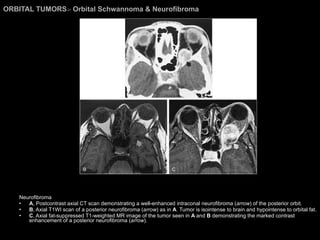

ORBITAL TUMORS >  Orbital Schwannoma & Neurofibroma Neurofibroma A , Postcontrast axial CT scan demonstrating a well-enhanced intraconal neurofibroma ( arrow ) of the posterior orbit.  B , Axial T1WI scan of a posterior neurofibroma ( arrow ) as in  A . Tumor is isointense to brain and hypointense to orbital fat.  C , Axial fat-suppressed T1-weighted MR image of the tumor seen in  A  and  B  demonstrating the marked contrast enhancement of a posterior neurofibroma ( arrow ).